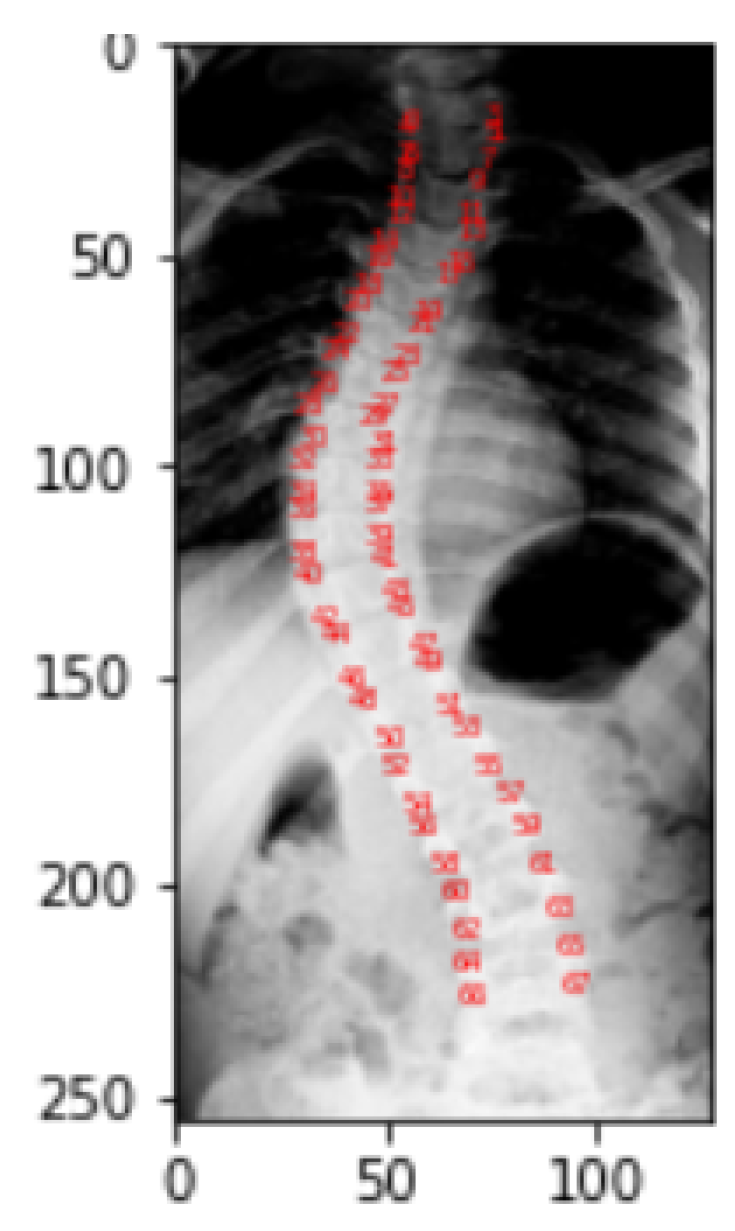

For each image instance, a corresponding mask will be generated using the landmarks provided in the CSV format of dataset. To understand how the landmarks, adjust to align with the spine portion of the image, a visualization is performed and this resulting visualization of the landmarks helps to create the mask.

2.3. Landmarks Visualization

This visualization is only done to help the viewer better see and comprehend the spine part of the X-ray picture. Figure 10 gives the visualization of landmarks. Landmark values of a picture correspond to the location of pixel in a particular image for which it is obtained. In the dataset, each picture in the landmarks file has CSV values that correspond to the pixel position in the specific image for which they were obtained. As a part of the representation process, these landmark values are transformed into arrays, which are then reshaped into two columns for a single picture as x and y coordinates, and finally mapped to pixel values.

To identify the spine portion, the land marking is performed by reading the image into arrays and converting theses array into two columns of x and y coordinates leading to the transformation into pixel values. Plot of these pixel values highlight the spine area. The red highlighted dash lines around the spine in Figure 17 refers to the landmarks of the spine.

Figure 10. Visualization of Landmarks on Original Images.

Figure 17. Visualization of landmarks.